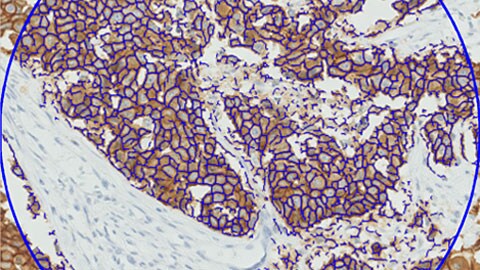

Digital pathology will open up new ways to get more information from tissue samples. The development of specific algorithms for automated interpretation of advanced stains will facilitate the objective analysis of images. By developing advanced algorithms and data management systems, we can help you translate the ‘Big Data’ promise into knowledge. This can be an important stepping-stone towards better health management and patient outcomes.

IntelliSite’s image analysis applications offer tools that provide exciting new insights for research pathologists. In addition to our advanced algorithms, the solution’s open platform has spawned the development of tools from several partners.

Philips is collaborating with Mount Sinai Health System in New York, NY to advance clinical research through the development of a new digital pathology repository and advanced analytics. By digitizing hundreds of thousands of tissue samples and combining these with related diagnostic data, treatment data, and outcome data, unique insights may enable the development of predictive analytics to help further personalize patient care for complex diseases, including cancer.